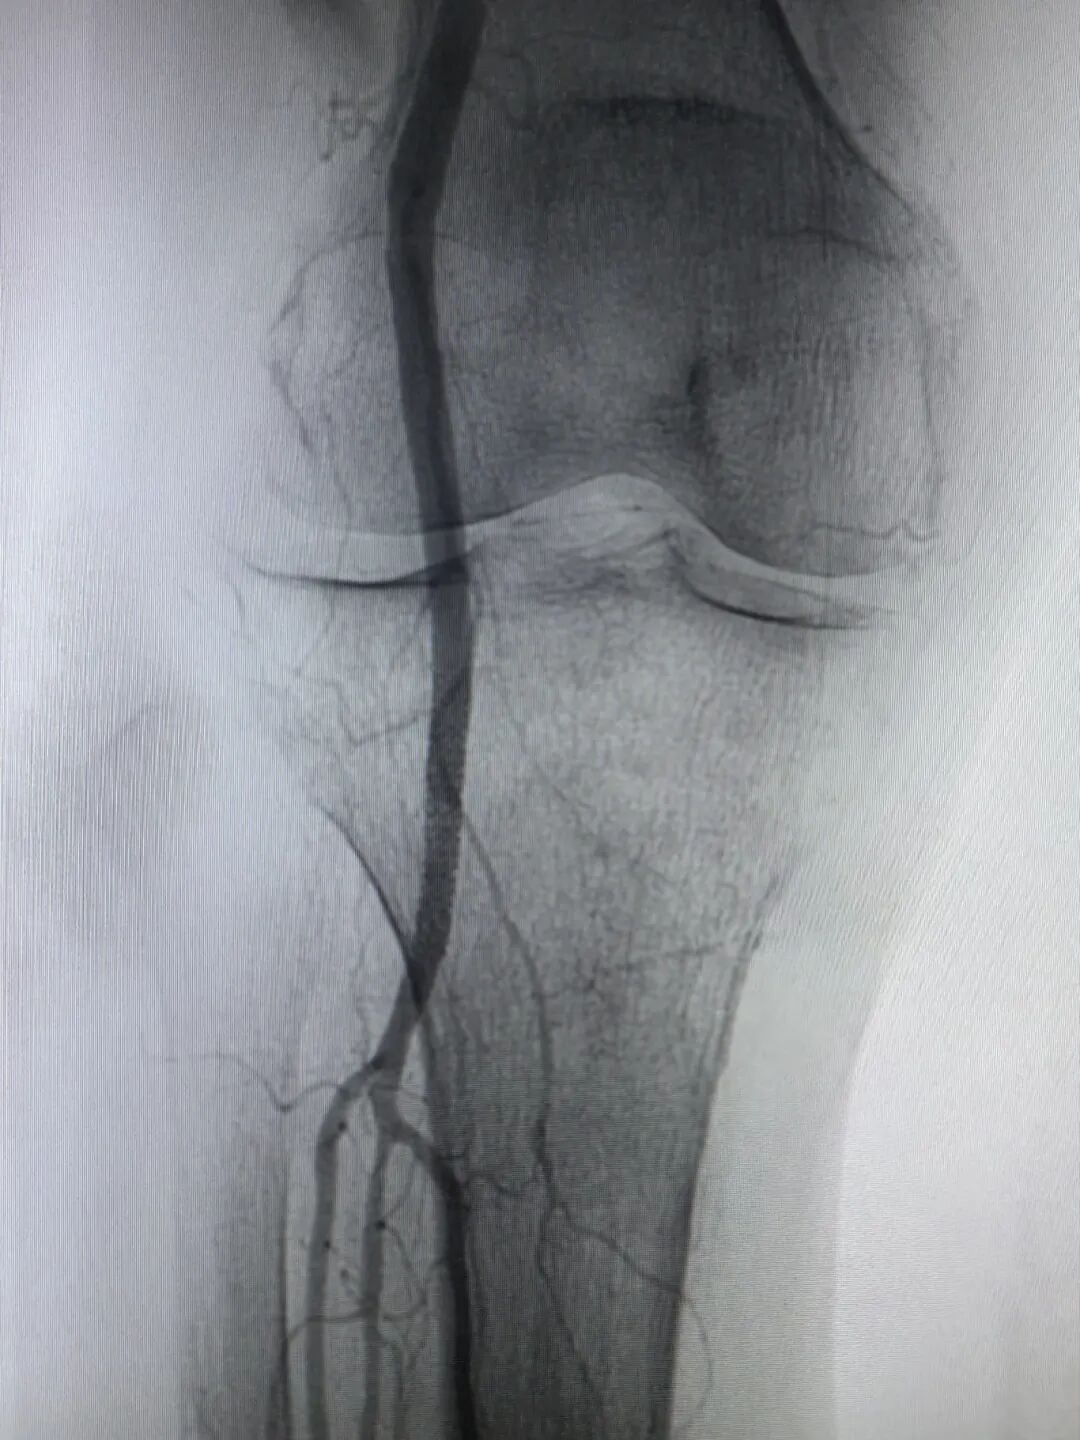

(介入术后闭塞的血管完全再通)

两个小时后,手术顺利完成。孙奶奶右下肢的皮温、皮色即刻改善,足背动脉搏动恢复,疼痛麻木消失。从入院到血运重建,全程高效顺畅,没有浪费一分一秒。